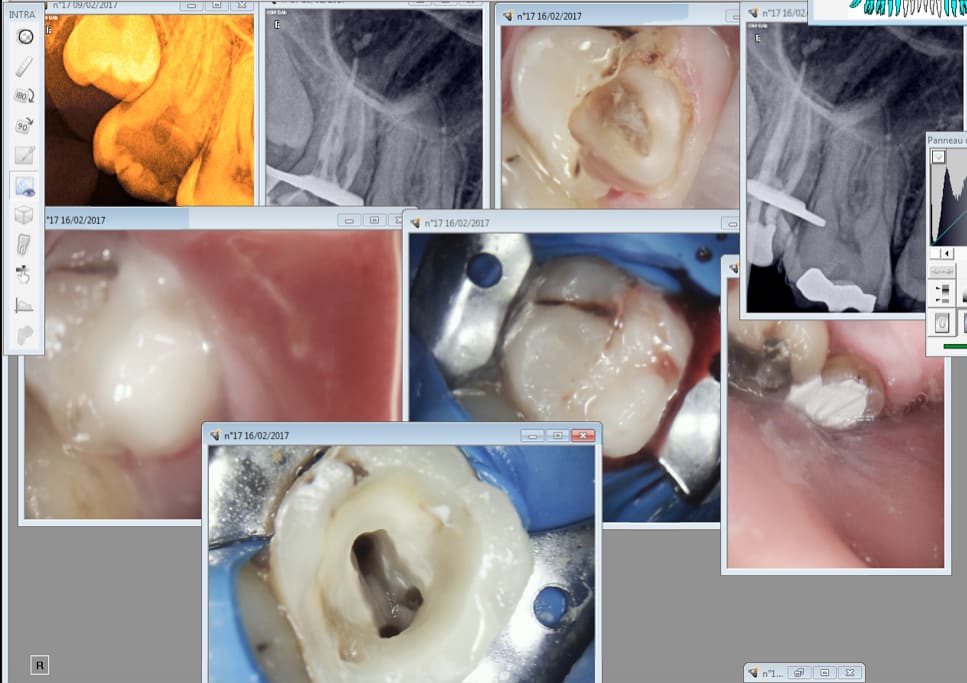

dans le cas d'une sensibilité persistante après quelques mois

et si la radio ne revele pas d'atteinte periapicale

il faut penser à une fêlure

une radio préop et une radio actuelle pourrait nous être utile pour t'aider

Putain des fois les racines palatines font la meme longueur que les racines vestibulaires. Un peu sur instrumenté + puff.

Ca tient bien les reconstitutions pré endos minute. Sans digue tu peux t'accrocher pour la faire celle là ! -)))

Chicot, pourquoi tu n'as pas simplement vire la 17 et laisser la 18 prendre sa place ? Dans ton cas et d'apres la radio, je suis presque sur que cela aurait pas mal fonctionne.